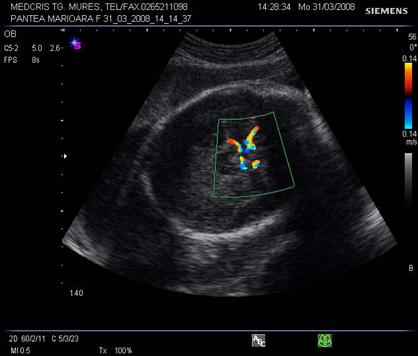

Fig. nr.329. Ductus venosus( sageata ) la o sarcina de 16 sapt,. sectiunea sagitala fetala

Fig. nr. 330. Ductus venosus la doppler pulsat cu CFM , la o sarcina de 27 sapt. Se remarca aspectul normal trifazic al undei .

Fig. nr. 331. Ductus venosus la doppler pulsat si CFM , la 21 sapt, fat in sectiunea transversala a stomacului